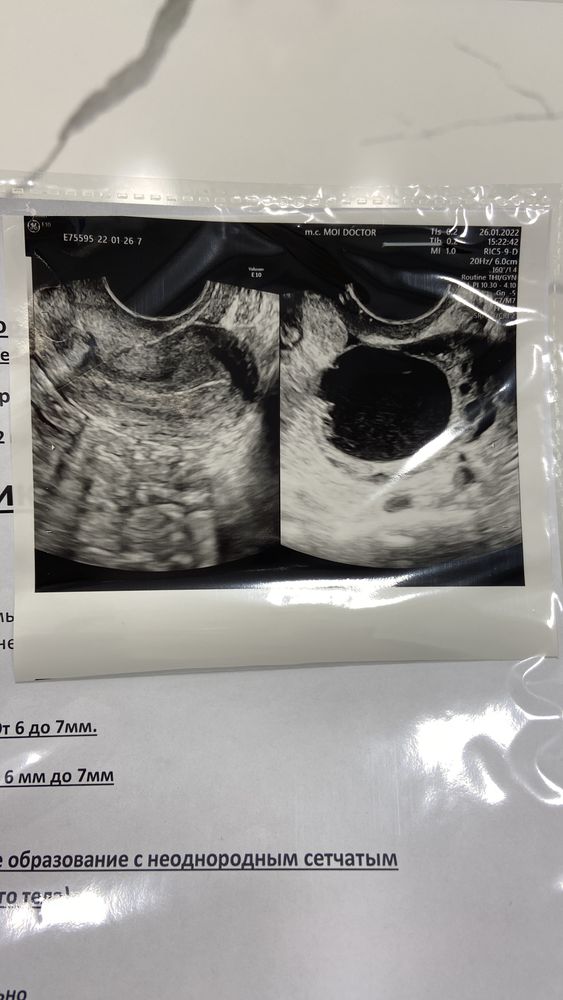

Девочки история будет длинной нужен ваш совет😓😓 Делала в этом месяце стимуляцию клостилбегит 100мг, и хгч 10т, фолликул был 18 в пятницу сделали укол, в субботу было чувство овуляции, сегодня ночью была капля крови и больше ничего тишина до сих пор, пошла сегодня на узи подтвердить овуляцию, там киста ЖТ, врач сказала фолликул чуть лопнул и что-то из него вышло, сказала про каплю крови, она сказала это имплантационное кровотечение, у кого было подобное поделитесь своими историями, ещё я делала стимуляцию в июле 21 года тогда тоже образовалась киста ЖТ